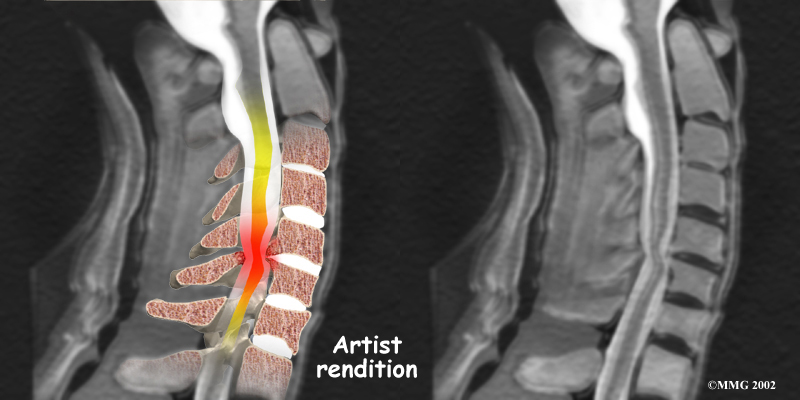

Spinal Stenosis

However, stenosis can also develop when a person of any age has a disc herniation that pushes against the spinal canal. When the spinal cord is squeezed in the neck, doctors call the condition cervical myelopathy. This is an alarming condition that demands medical attention. Cervical myelopathy can cause problems with the bowels and bladder, change the way you walk, and affect your ability to use your fingers and hand.

Cervical Myelopathy

The magnetic resonance imaging (MRI) scan uses magnetic waves to create pictures of the cervical spine in slices. The MRI scan shows the cervical spine bones, as well as the soft tissue structures such as the discs, joints, and nerves.

MRI scans are painless and don't require needles or dye. The MRI scan has become the most common test to look at the cervical spine after X-rays have been taken.